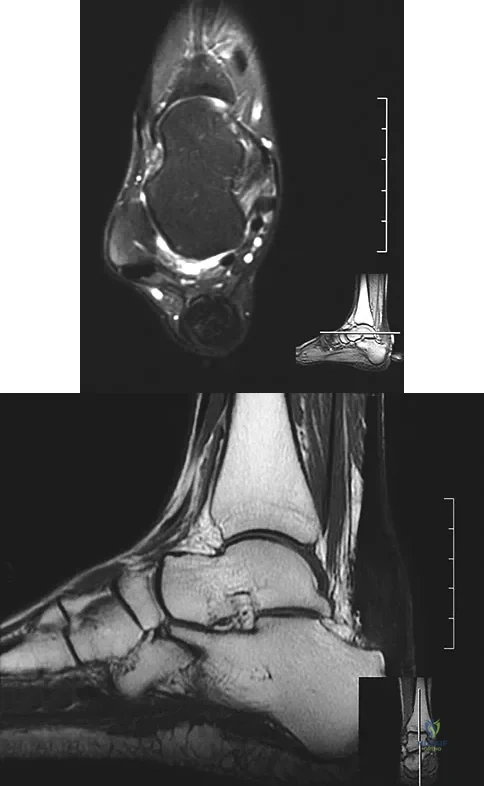

An 83-year-old woman with a long history of her foot slowly and progressively "turning out" now reports significant ankle pain. History reveals that she has significant cardiac disease and exercise-induced angina. Examination reveals a deficiency in the posterior tibial tendon; however, the hindfoot remains moderately supple. Radiographs reveal a valgus tilt of the tibiotalar joint and early arthrosis. What is the most appropriate orthotic management?

The patient will continue to have pain secondary to the ankle arthrosis with both the UCBL and the molded articulated ankle-foot orthosis. The total contact orthotic does not provide enough hindfoot control to support the progressive collapse of the ankle into valgus positioning. A molded leather gauntlet will not only control tibiotalar motion but also control hindfoot motion and allow support of the longitudinal arch.

An 8-year-old boy with severe hemophilia A (factor VIII) and no inhibitor is averaging eight transfusions per month for bleeding into the right ankle. Examination shows synovial hypertrophy; range of motion consists of 0 degrees of dorsiflexion and 20 degrees of plantar flexion. The patient's knees, elbows, and left ankle have no restriction of motion. Standing radiographs of the right ankle are shown in Figure 18. Management should consist of

The patient has bilateral hypertrophic synovitis that is causing repeated hemarthroses and progressive arthropathy. Ankle synovectomy in patients with hemophilia is effective in significantly reducing the rate of joint bleeding and in slowing the progression of the arthropathy; therefore, bilateral synovectomies is the treatment of choice. Range of motion can be effectively maintained after ankle synovectomy. Bracing and prophylactic transfusions would be ineffective at this time. Ankle arthrodesis should be reserved for patients with severe pain. Compared with patients who have juvenile rheumatoid arthritis, patients with hemophilia generally do not have involvement of the subtalar joint and rarely require a pantalar arthrodesis. Greene WB: Synovectomy of the ankle for hemophilic arthropathy. J Bone Joint Surg Am 1994;76:812-819.